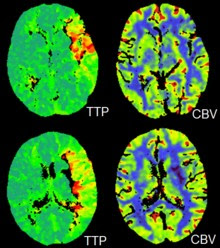

CT perfusion imaging

CT perfusion imaging is a specific form of CT to assess flow through blood vessels whilst injecting a contrast agent. Blood flow, blood transit time, and organ blood volume can all be calculated with reasonable sensitivity and specificity. This type of CT may be used on the heart, although sensitivity and specificity for detecting abnormalities are still lower than for other forms of CT. This may also be used on the brain, where CT perfusion imaging can often detect poor brain perfusion well before it is detected using a conventional spiral CT scan. This is better for stroke diagnosis than other CT types.